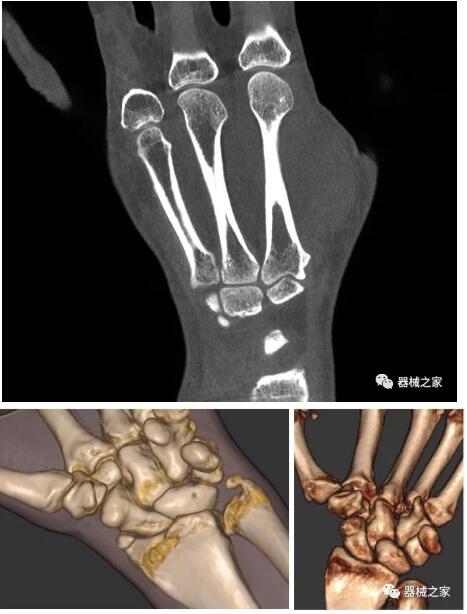

以上介紹的CT均來自國外同一家公司,這些CT均配置了可視化軟件,可以進(jìn)行切片、3D重建以及大型CT附帶的所有典型的操作功能。

當(dāng)然,這類充滿想象力的CT,國內(nèi)也有生產(chǎn)廠家在研究,比如賽諾威盛研發(fā)的InsitumCT Zero,可以很好的適應(yīng)特殊的臨床應(yīng)用場景,超大孔徑多種自由度組合,可實(shí)現(xiàn)水平和垂直等多種掃描模式。

對于急診外傷患者,它縮短了診斷到治療的路徑,避免移動患者帶來的二次損傷;復(fù)合手術(shù)室中,它可以讓醫(yī)生第一時(shí)間確認(rèn)或調(diào)整手術(shù)方案,大大縮短手術(shù)時(shí)間;對于需要放療定位、質(zhì)子治療的患者,一站式的定位、治療服務(wù)能夠更加精準(zhǔn)。

以下是這些“特立獨(dú)行”的CT所拍出來的圖像: